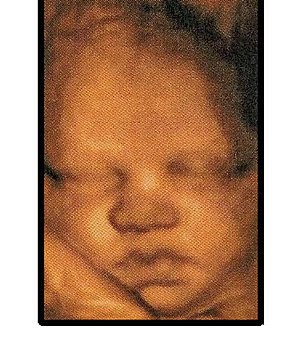

3d ultrasound video at our Strathpine location 3d Baby Precious Previews PreciousPreviewsAU. Subscribe Subscribed Unsubscribe 0 0. Loading 3D & 4D Ultrasound Buffalo, NY - Duration: 3:12. PerfectPreview3D4D 260 views. 3:12 ... View Video

Millard Fillmore Suburban Hospital - Buffalo Baby

Millard Fillmore Suburban Hospital offers outpatient screening for expecting mothers including 3D ultrasound and Nuchal Millard Fillmore Suburban Hospital greatly encourages the “Golden Hour” of 716-558-saFE or visit fjcsafe.org located at 237 Main St 14th floor, Buffalo, NY ... Document Viewer